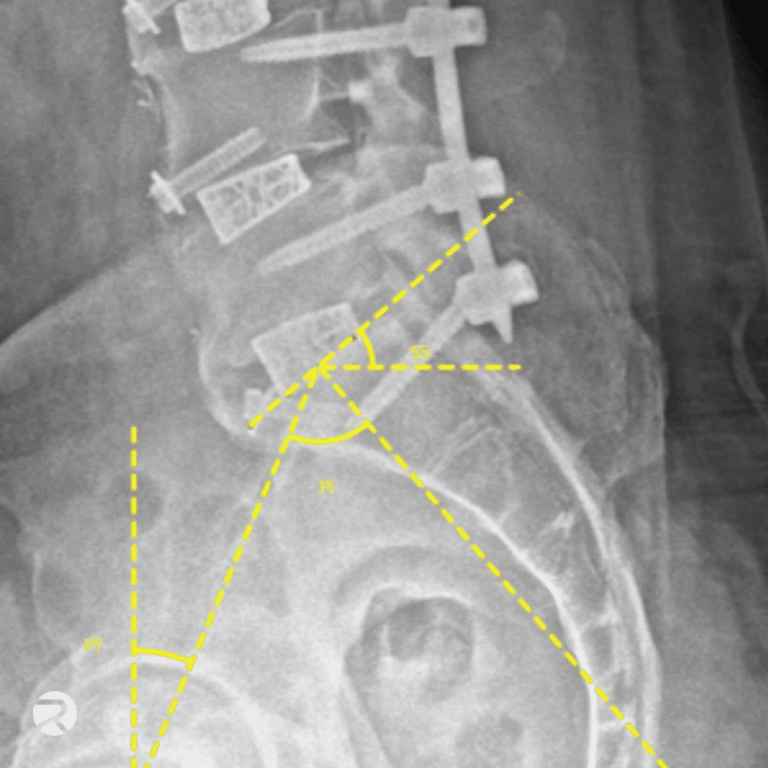

Präzise, zuverlässige und reproduzierbare Messungen der Wirbelsäulenbildgebung

Führen Sie schnelle, hochpräzise Messungen wichtiger morphologischer Wirbelsäulenparameter (z. B. Cobb-Winkel, Lordose) durch, die als Endpunkte zur Bewertung aller zentralen Wirbelsäulentherapien dienen – von bewegungserhaltenden Verfahren über Fusion bis zur Deformitätskorrektur – und erhalten Sie verlässliche, robuste und kosteneffiziente Messdaten für die klinische Forschung.

Wirbelsäule

- Bewegungsumfang (Range of Motion, RoM)

- Rotationszentrum (Center of Rotation, CoR)

- Bandscheibenhöhe

- Anteroposterior-Instabilität

- Cobb-Winkel

- Zervikal- und Lumbarlordose

- Segmentale Bewegungsanalyse

- Fusionsbewertung

- Implantat-Subsidence

- Und über 100 weitere Parameter

Präzise Messungen der Wirbelsäulenmorphologie sowie der Implantatpositionierung und Implantatleistung.

● Wirbelsäulenmessungen

Angular Range of Motion (RoM, °)

Anteroposteriore Translationsbewegung (Anterposterior Translational Movement)

Cobb-Winkel

● Leistungsmetriken für Wirbelsäulenimplantate

Implantatsenkung (Implant Subsidence)

Wiederherstellung des Lordose-/Kyphosewinkels

Wirbelkörperhöhe